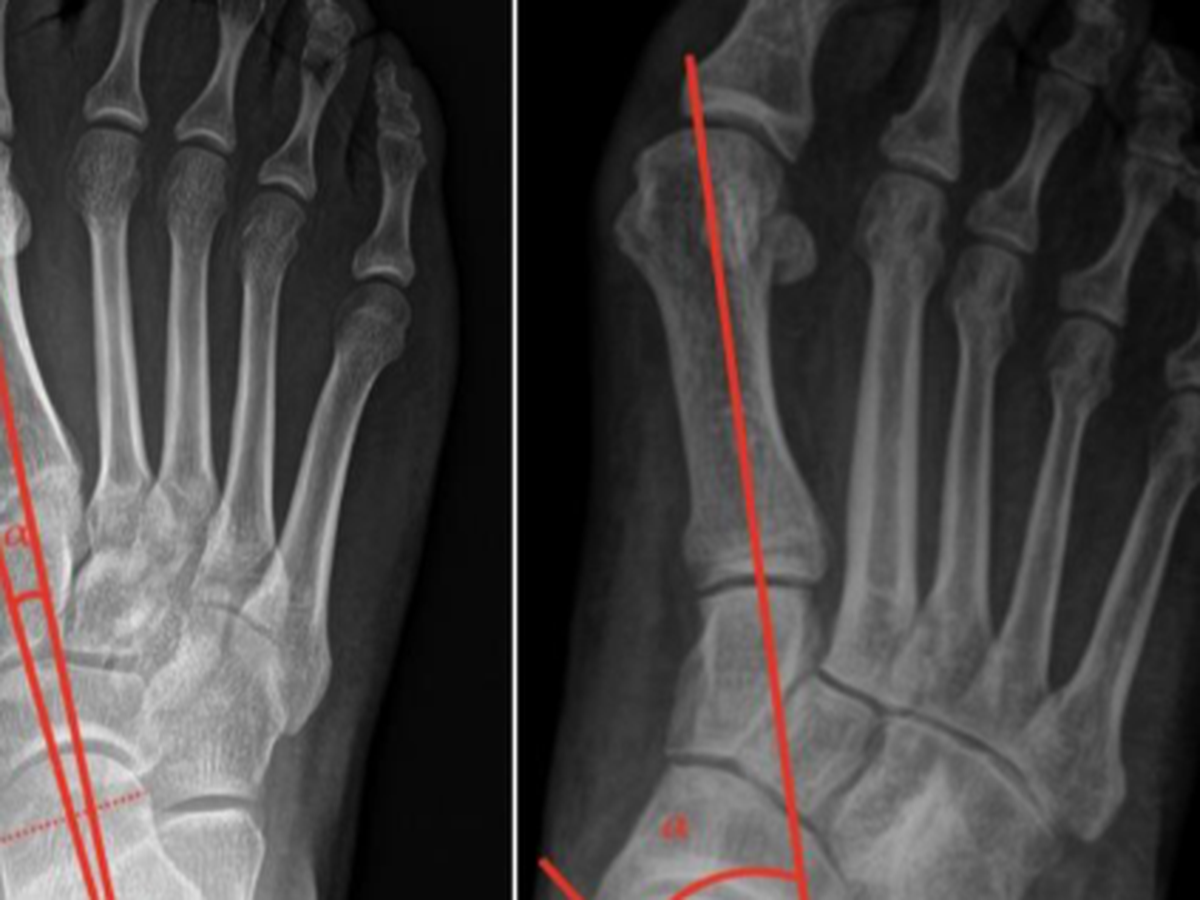

Ramtin has two flat feet. As he grew, it was hoped that special inserts would resolve this issue, but it hasn’t. He walks with pain, and the condition is now also affecting his back.